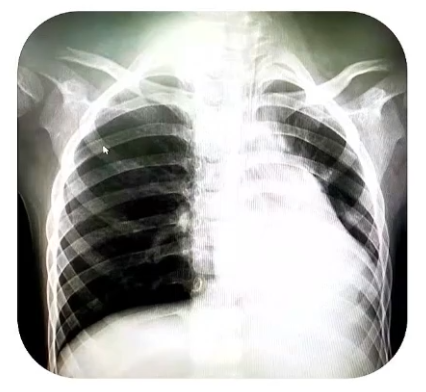

2020年10月4日,①床旁超声评估膈肌功能(更换为PSV模式):膈肌移动度明显减弱,呼吸频率增快;②咳嗽功能明显减弱:吸痰刺激无咳嗽反射,咳嗽功能0级,痰液量多,稀薄;③床旁胸部X线片:右肺上叶不张或实变,右侧膈面稍抬高。

2020年10月20日,患儿床旁超声显示膈肌活动度较前改善;床旁胸部X线片显示肺部感染较前加重,右侧膈面抬高;体温正常。咳嗽功能明显改善,1~2级,痰液量较前减少,每3小时需吸痰1次。根据患儿能量代谢测定结果调整肠内外营养,将镇静药物咪达唑仑改为右美托咪定,加强气道管理,继续使用咳痰机和体位治疗。调整呼吸机模式,间断使用PSV模式进行呼吸锻炼。在康复方面加用了穴位针灸治疗。